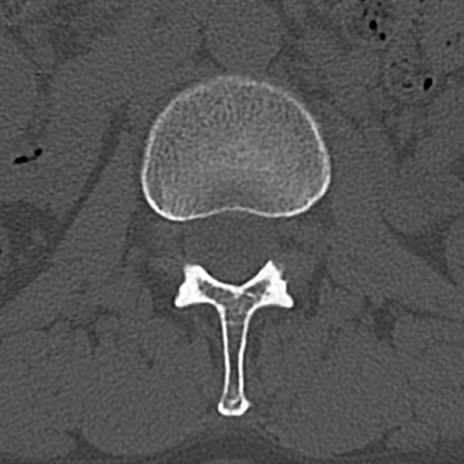

【整形】TIPS症例4 腰椎CT(横断像)

腰椎CT

横断像と矢状断像